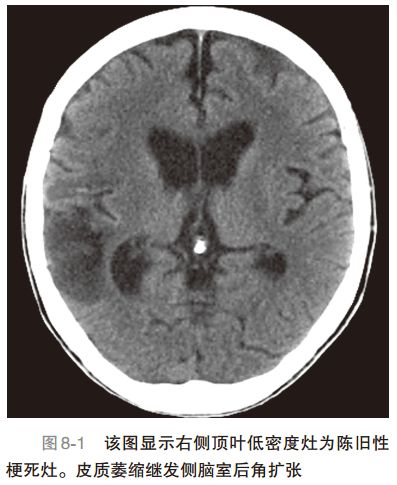

2. 怀疑ICH,如剧烈升高的血压、头痛、呕吐,可能合并困倦、血小板计数减低、凝血功能障碍,使用抗凝剂或使用兴奋剂药物(图 8-3为ICH颅脑CT)。